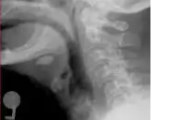

Sialolitiaas (süljekivi)